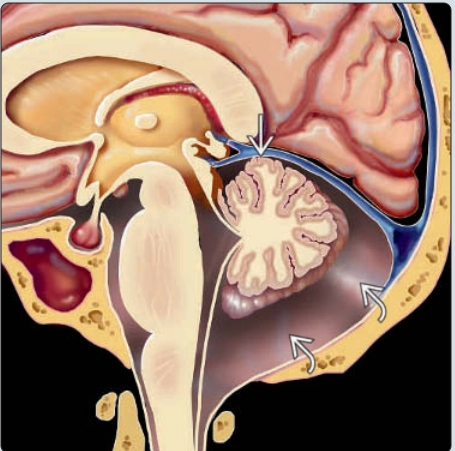

Dị dạng Dandy-Walker ở thai (Classic Dandy-Walker malformation)